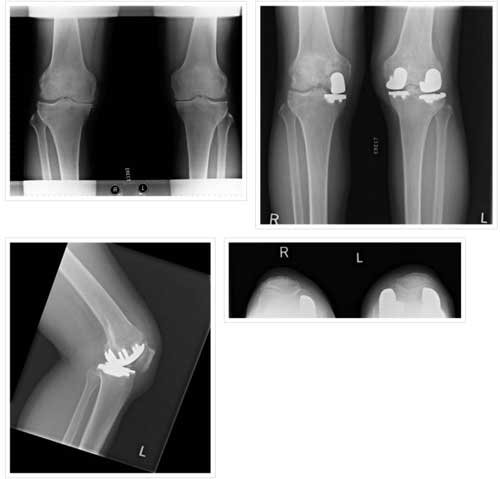

PATELLOFEMORAL ARTHRITIS IN- 40 YEAR OLD FEMALE

PATELLOFEMORAL REPLACEMENT-POSTOP

BILATERAL PATELLOFEMORAL REPLACEMENT

BILATERAL PATELLOFEMORAL REPLACEMENT

LATERAL VIEW

BICOMPARTMENTAL INVOLVEMENT

BICOMPARTMENTAL REPLACEMENT

Bicomp in 55 yr

Bicomp 47yr

BICOMP-POST OP

Medial compartment involvement

Right medial and left bicomp

Right UKA, Left bicomp

left medial and lateral few years apart